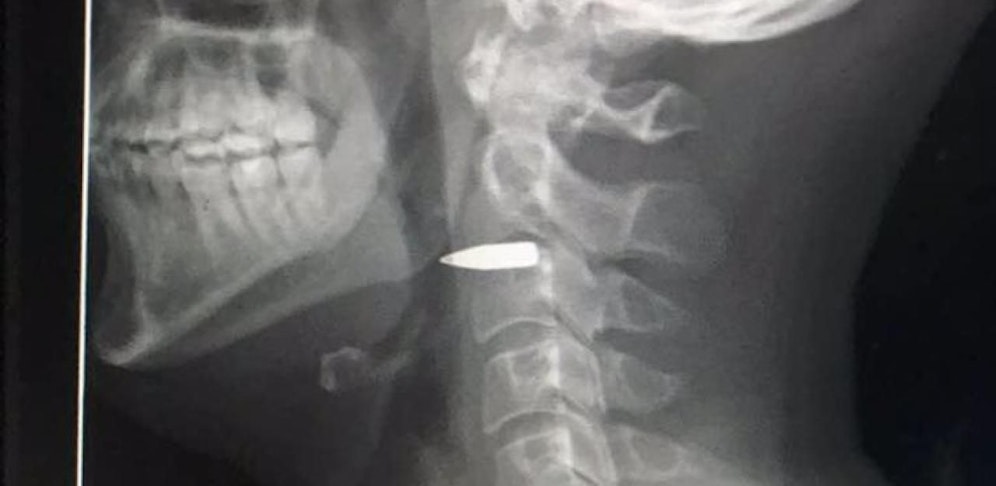

Glücklicherweise verfehlte das Geschoss heikle Gefässe und Nerven knapp. Harvey selbst twitterte ein Foto vom Röntgenbild und sich selbst mit erhobenem Daumen. Es gehe ihm gut, allerdings: "Die Kugel steckt noch immer in meinem Nacken."